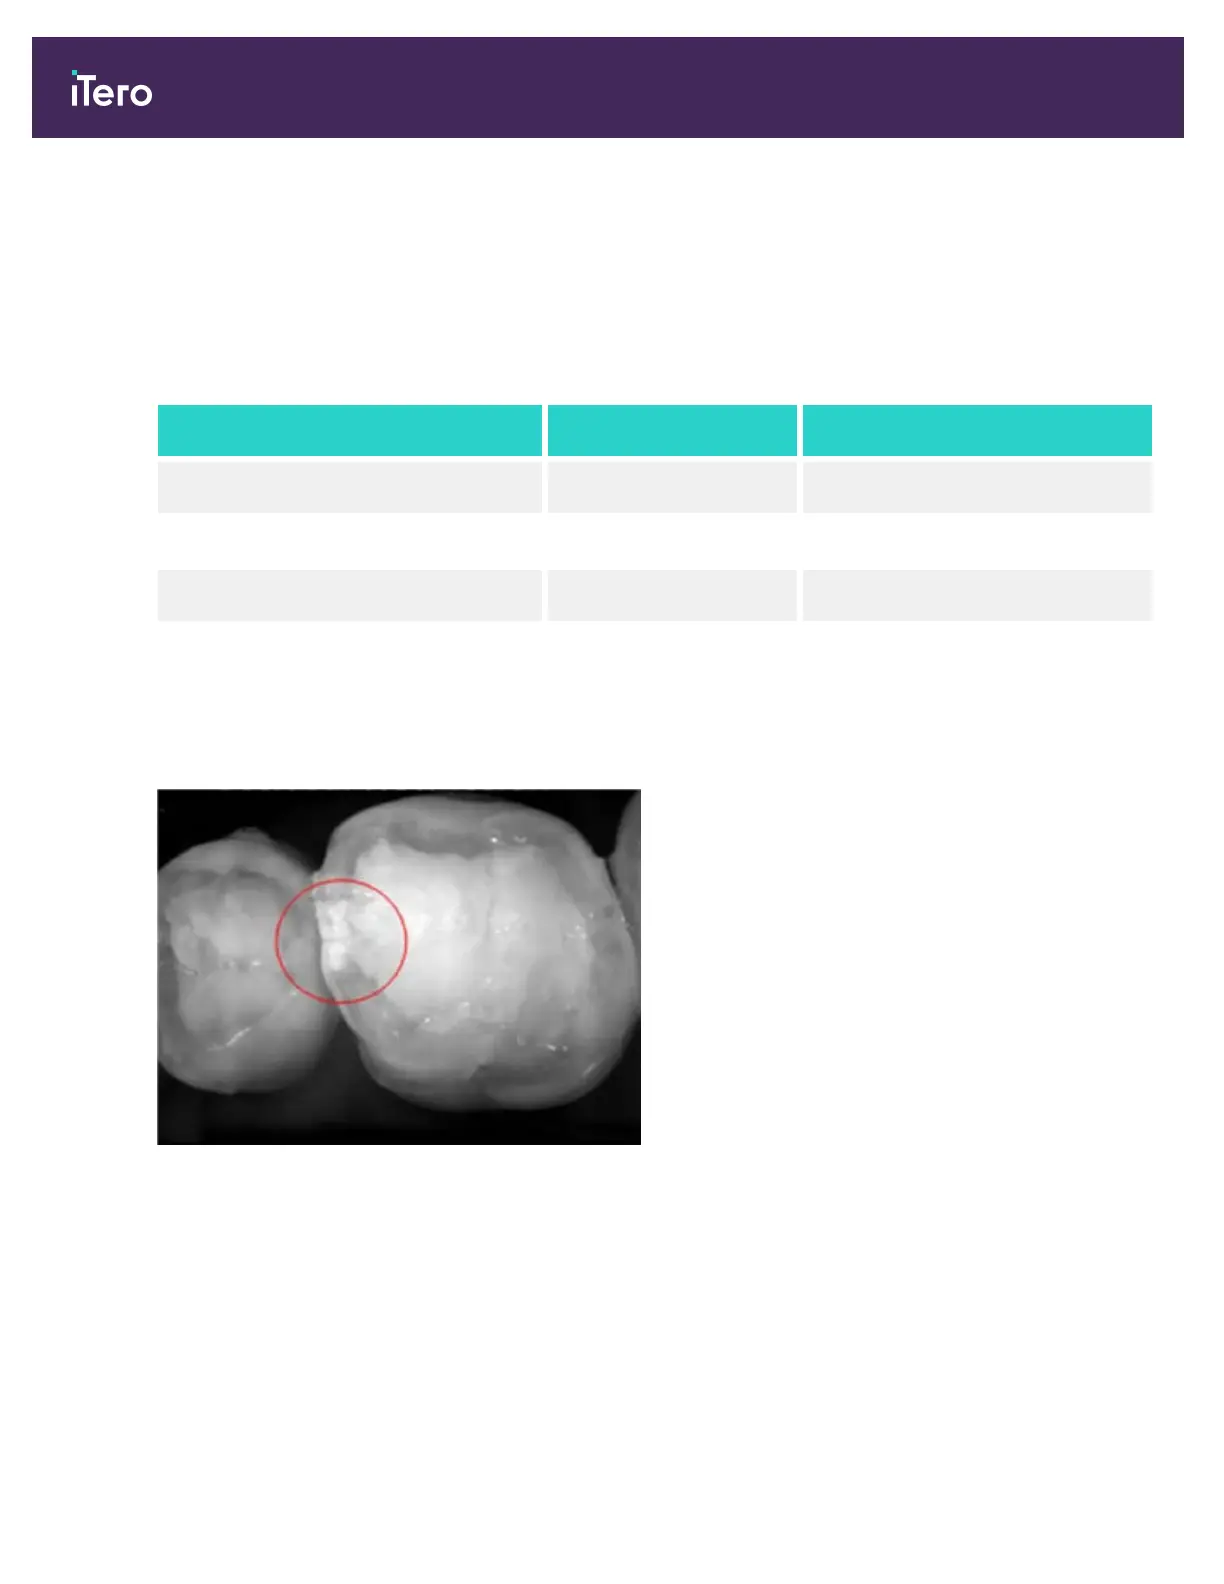

The resulting NIRI grayscale image shows structures with varying translucency as different levels of brightness. The

lower the translucency, the higher the reflection of the infrared light and the brighter the structure. Using this

technology, it is possible to make out the following structures:

Appears Translucency

Enamel Dark High

Interproximal caries Bright Low

Dentin Bright Low

The differentiation between carious lesions and dentin is based upon the location of the bright feature. Dentin is

located in the center of a tooth, whereas interproximal carious lesions appear on the interproximal or distal mesial

region, where healthy enamel is expected.

As such, dentin and interproximal carious lesions appear as bright features, with a dark enamel ring around the dentin

structure, as shown in the figure below, which provides an occlusal view of a carious lesion.

Figure 8: Interproximal carious lesion